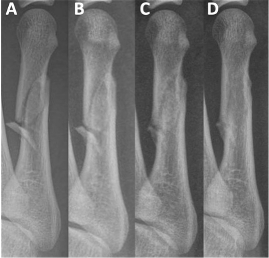

Evaluating the syndesmosis usually starts with standard X-rays, the AP view, and we look at the amount of overlap between the fibula and the tibia as a guide to determining how much of the syndesmosis is torn.

When these two bones are separated, that's usually a good indication that syndesmosis is damaged. Now, we usually see this with the Weber C fibular fractures, but there are criteria that we can use to evaluate the extent of damage to the syndesmosis. So that decision probably should be made prior to the patient getting on the operating room table. And many times with standard X -rays, you can determine if the syndesmosis is torn by looking at the amount of separation between the fibula and the tibia. However, if you're not sure if the results of the X-ray examination are variable, we can always get a CT scan for further evaluation.